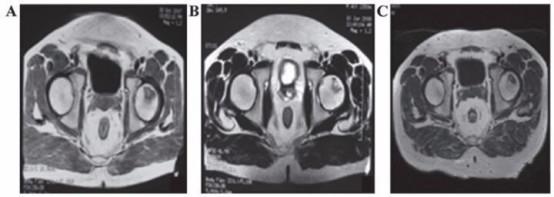

科学研究发现,干细胞能够改善缺血性脑损伤和脑瘫动物模型的运动功能。在杜克大学开展的这项交叉试验中,63名脑瘫患儿被随机安排静脉注射干细胞或安慰剂,并在1年后进行交替注射。治疗1年和2年后,研究人员开展了运动功能和磁共振脑连通性研究。结果发现,适当剂量的干细胞注射可以改善脑瘫儿童的大脑连通性和运动功能。

在我国,干细胞治疗脑瘫同样进入了临床试验阶段。2016年,*警武**浙江总队嘉兴医院团队在《*警武**医学》杂志上报道了11例自体间充质干细胞移植治疗脑瘫的2年随访结果,证实了间充质干细胞转化神经干细胞移植治疗脑瘫的安全性和有效性。患儿运动功能改善在干细胞移植3个月后明显显效,6个月后运动康复效果逐渐消失,但运动能力无*退倒**现象;患儿语言功能改善在干细胞移植6个月后显效,12个月后语言快速改善效果消失,但没有语言能力的*退倒**。